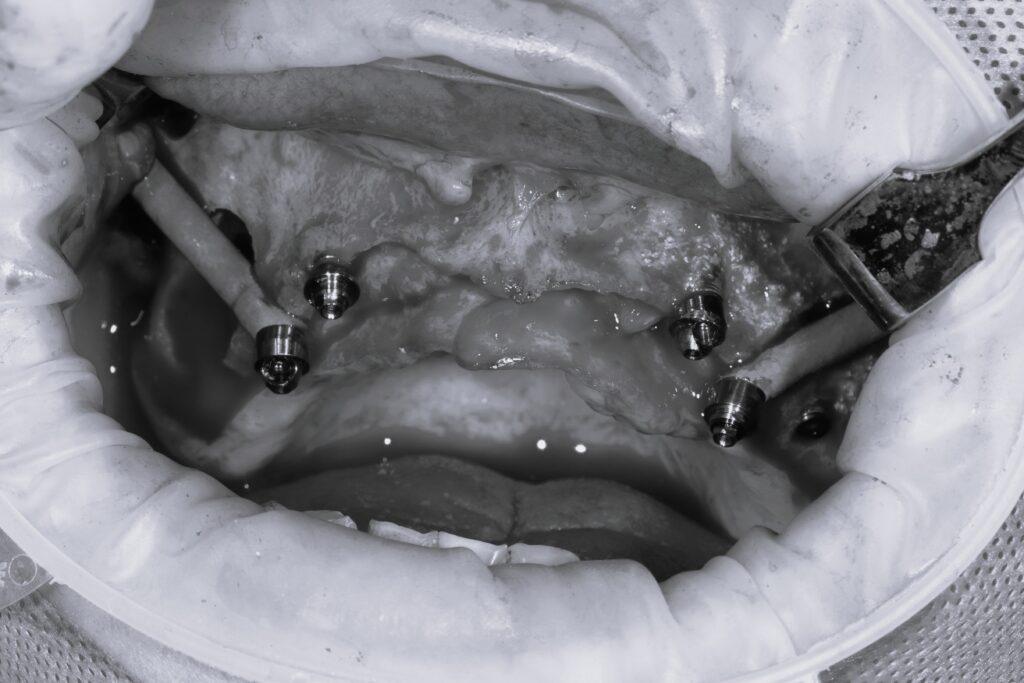

- 整個上顎骨嚴重萎縮者:可能需使用兩支或四支顴骨植體,搭配前方的普通植體,形成所謂的 Zygoma + All-on-4 混合系統(Hybrid Concept)。

✅ 2. 一天完成臨時咬合

搭配 All-on-4 概念,可實現 「即拔即種即戴牙」,重拾笑容與生活自信。

阿德,45歲,曾做過3次補骨手術皆失敗,咬合崩壞。經評估後,使用顴骨2支+All-on-4植體,1天完成拔牙與臨時假牙裝戴。三個月後安裝正式牙橋,至今使用超過5年。